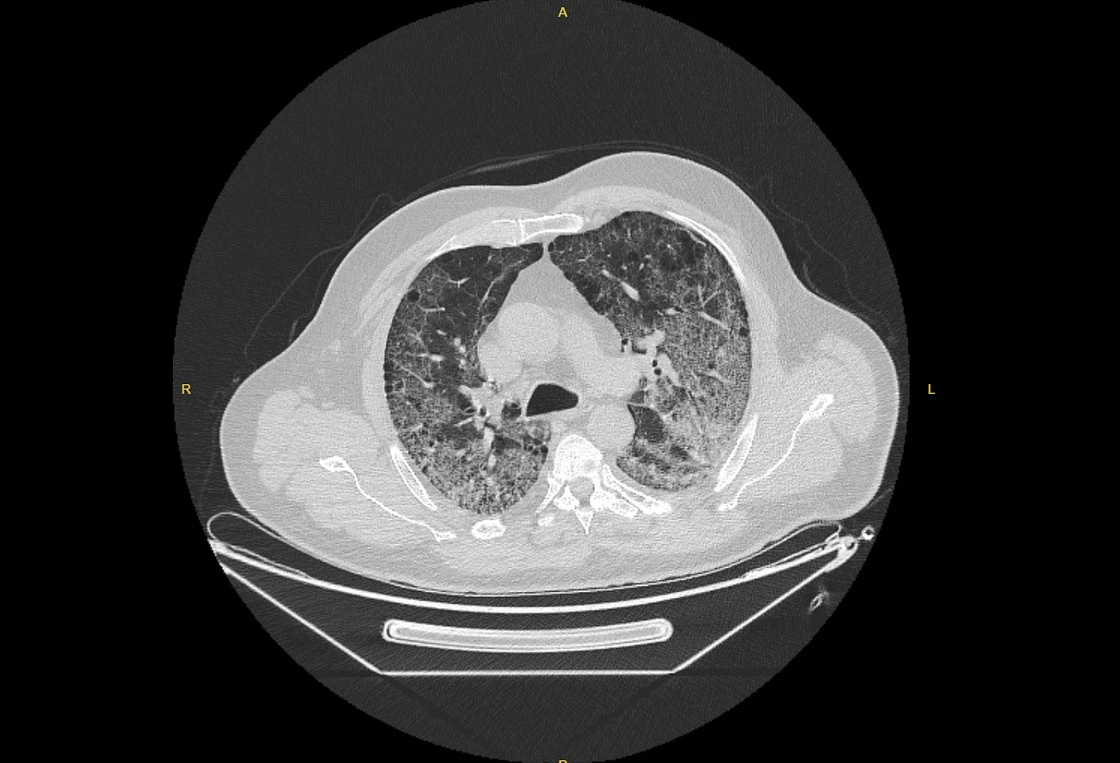

Kliniğe yeni başvuran bir hastanın, 5 Ağustos'ta çekilen tomografi görüntülerindeki tipik koronavirüs görüntülerinin olduğunu ifade eden Karalezli, hastanın bir hafta içerisindeki tomografi görüntüsünde ciddi değişiklik olduğunu ve enfeksiyonun çok arttığını söyledi.